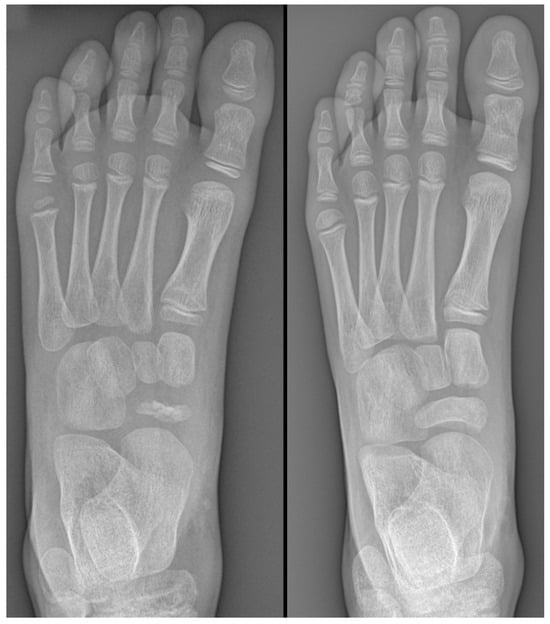

Sometimes, navicular osteochondrosis can be an incidental finding on radiographs with no focal tenderness or pain. When pain is reported, the primary diagnostic tool is radiographic imaging. Regarding the role of radiographs in the study of navicular osteochondrosis, Mouchet and Roederer wrote, “The clinical presentation is almost negligible, radiography is everything.” [33]. Initial radiographs may show signs of bone sclerosis, which is indicative of altered bone metabolism and insufficient blood supply. The radiographic findings can range from subtle changes to more evident deformities, depending on the stage of the disease. In doubtful cases, it is helpful to perform a comparative radiograph of the contralateral healthy foot. Over time, radiographs may reveal a characteristic collapse and flattening of the navicular bone. In advanced forms, the navicular becomes very thin, exhibiting a biconcave or knife-blade appearance. The radiographic appearance of the navicular takes a long time to return to normal after healing, often requiring 1 to 2 years [14] (Figure 6).

Figure 6.

(Left): Radiograph of a 6-year-old male patient showing characteristic collapse and flattening of the navicular bone. (Right): Radiograph at 2-year follow-up after conservative treatment with non-weight-bearing casting, demonstrating good restoration of the navicular bone’s anatomical profile.

Advanced imaging techniques such as MRI may occasionally be used to further assess the extent of bone involvement or to rule out other conditions, such as infections or neoplastic processes. MRI, in particular, can provide detailed images of both bone and soft tissue and may be useful in detecting early bone marrow edema, a feature that may not be visible on plain radiographs [34].